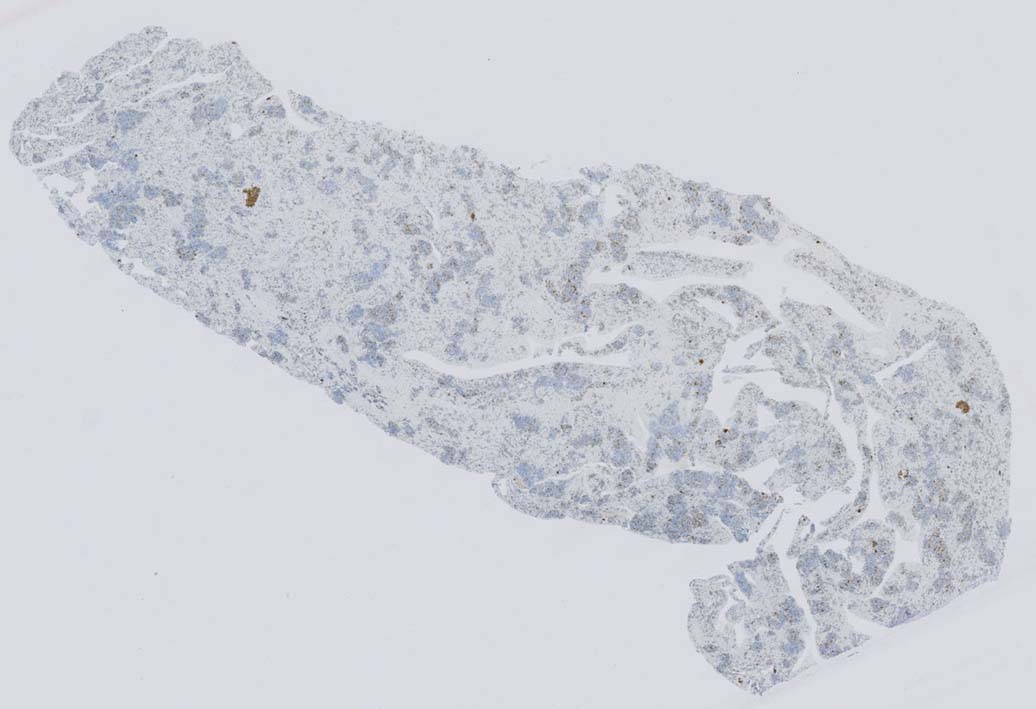

肝臓  サムネイルのクリックで大きな画像が見られます.

肝針生検組織; 類洞に細胞浸潤が認められ, 非浸潤部との境界がぼんやりと認められる. 類洞と異なり, グリソン鞘は腫瘍細胞の浸潤が乏しいか, ほとんど認められない.

類洞内に浸潤増殖するリンパ腫細胞: 類円形・長円, 瓜状の核をもつ,細胞質の乏しい細胞(サムネイル画像のクリックで大きな画像が見られます)

類洞内で増殖する腫瘍細胞はCD3+, CD7+のT-cellであるがCD5発現が弱く, 異常なT-cellである.

CD4は類洞内皮/macrophageの一部が陽性であるが, 類洞内腫瘍細胞の多くは陰性を示す(陽性と間違えないこと). CD8陰性. CD20陽性リンパ球はごく少ない.

TIA1は陽性であるが, granzymeBは陰性細胞が多い.